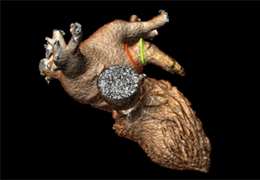

ANYTHINK 经导管主动脉瓣膜置换术分析系统